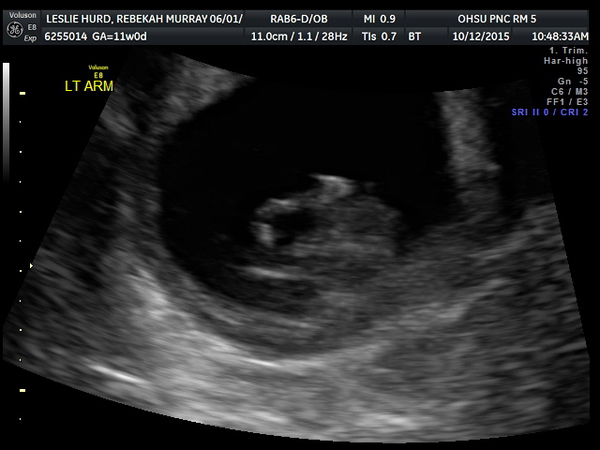

11 Week Ultrasound

Monday 12 October 2015